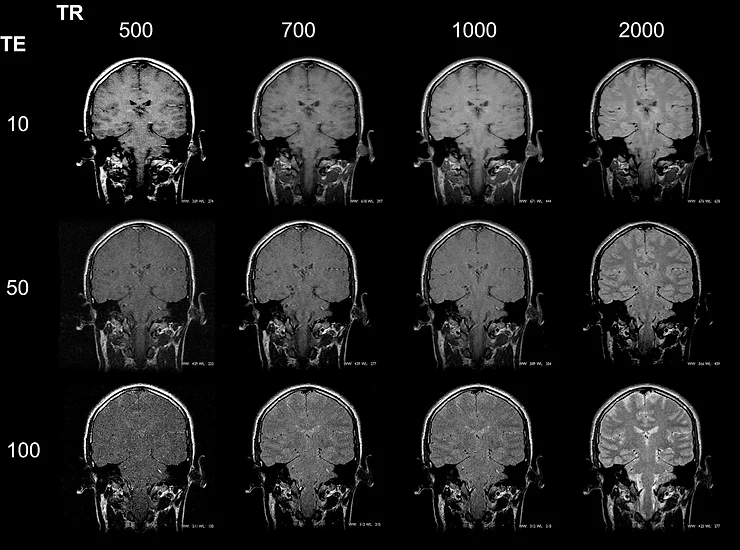

Portanto, os parâmetros TR e TE estão diretamente relacionados no processo de formação de imagens, interferindo no contraste e na qualidade das imagens dos diferentes tipos de tecidos e elementos do corpo humano. Confira os resultados de diferentes interações entre TR e TE:

Fig. 5 - Diferentes aplicações de TR e TE geram diversos resultados de contraste.

- TR curto e um TE curto produzem uma imagem ponderada em T1 (Ex. TR = 500 ms e TE = 10ms), ou seja, mostra melhor as diferenças de relaxação T1 entre os tecidos;

- TR longo e um TE longo produzem uma imagem ponderada em T2, ou seja, é a informação da diferença na relaxação T2 que mais influenciará a geração de sinal na bobina.